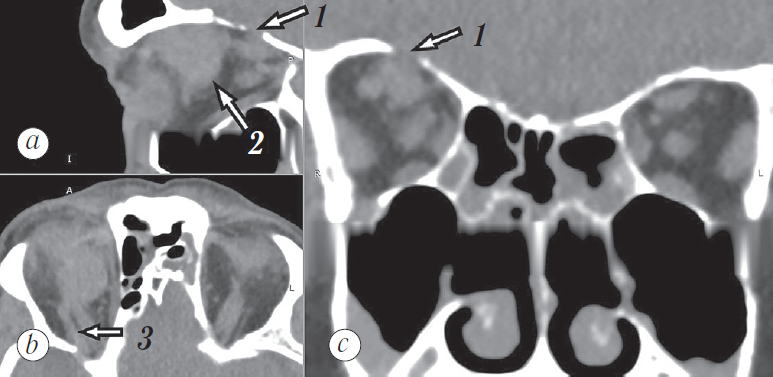

По данным КТ в полости правой глазницы от переднего верхнемедиального отдела до вершины глазницы располагается объёмное образование овальной формы, с чёткими ровными контурами размером 20,5 × 19 × 19 мм, плотностью 50–83 HU, интимно прилежащее к верхней прямой мышце, оттесняющее кпереди глазное яблоко и латерально — зрительный нерв (рис. 10).

При анализе КТ головы заподозрено наличие дефекта верхней стенки правой глазницы. По этому поводу пациент консультирован нейрохирургом.

Рис. 10. Компьютерная томограмма глазниц в сагиттальной (a), аксиальной (b) и корональной (с) проекциях. 1 — предполагаемое место дефекта верхней стенки глазницы, 2 — новообразование глазницы, 3 — тяж к новообразованию глазницы (указано стрелкой)

Fig. 10. Computed tomogram of the orbits in the sagittal (a), axial (b) and coronal (с) projections. 1 – suggested location of the upper orbital wall defect, 2 – orbital neoplasm, 3 – band to the orbital neoplasm (arrow)

На 7-е сутки после операции выполнена контрольная КТ с последующим введением контрастного вещества. Состояние после эмболизации собственной сосудистой сети новообразования правой орбиты. В верхнемедиальном отделе преимущественно внутриконусного пространства правой орбиты визуализируются множественные участки эмболизированной артериовенозной мальформации (рис. 18, 1) с наличием выраженных артефактов. Между ретробульбарным сегментом зрительного нерва и медиальной прямой мышцей глаза сохраняется участок мягкотканного компонента округлой формы размером 6,0 × 7,0 мм, плотностью при нативном сканировании +50…+55 HU, после контрастирования +65 HU (рис. 18, 2) без признаков эмболизации.

Рис. 18. Компьютерная томография после эмболизации собственной сосудистой сети новообразования правой глазницы. На сагиттальной (a) и корональной (c) проекциях визуализируются артефакты в полости эмболизированного новообразования (1). На аксиальной проекции (b) определяется часть интактного (неэмболизированного) новообразования (2)

Fig. 18. Computed tomography after embolization of the proper vascular network of the right orbital tumor. On sagittal (a) and coronal (c) projections, artifacts in the cavity of the embolized neoplasm are visualized (1). On the axial projection (b), a part of an intact (non-embolized) tumor is revealed (2)